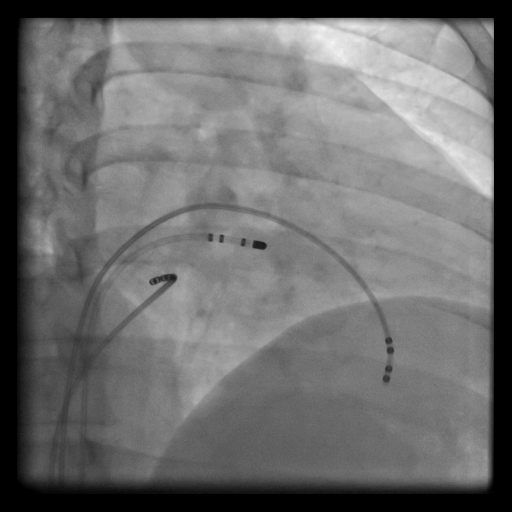

RF ablasyon tedavisi patolojik çarpıntıların tamamen ortadan kaldırılmasını sağlayan %98-100’e yakın başarı ihtimali olan bir tedavi yöntemidir. Kasıktan toplar damara girilerek kalbe ulaşılır, yaklaşık ½-1 saat süren ağrısız bir işlemdir. Çarpıntı yapan odak saptanarak (elektrofizyolojik çalışma) burası yüksek frekanslı ses dalgaları ile ısıtılır ve tahrip edilir. Bu tedaviden sonra hastaların ilaca ihtiyaç duymaması ve çarpıntı şikâyetinin yok olması en büyük kazançtır.

- Çarpıntı Tedavisi- RF (Isıtarak) Ablasyon

- Çarpıntı Tedavisi-CRYO (dondurarak) AF Ablasyonu